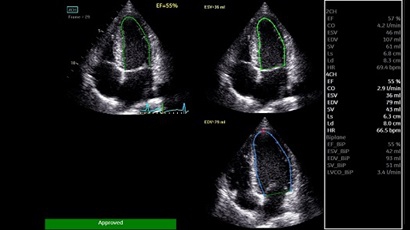

AUTO 2D EF:

Да

• AUTO 2D EF - режим автоматической недопплеровской количественной оценки глобальной сократительной функции ЛЖ (по Simpson).

• AFI - режим цифровой недопплеровской качественной и количественной оценки региональной сократительной функции ЛЖ.